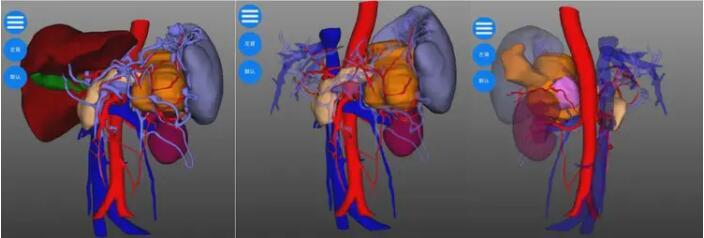

由于患者瘤体巨大,侵及周围脾、肾上腺、结肠、胃、十二指肠等多个脏器器官,手术难度极高,翟博教授随即请科室主任谭刚教授会诊,基于对患者病情分析及为降低手术风险,完善胰腺三维成像,得以精准定位肿瘤位置及周围血管分布,精准规划手术流程。

谭刚教授仔细研究了赵大娘的病情,认为肿瘤虽然涉及多个脏器,但尚未发生远处转移,为挽救患者生命,谭刚教授毅然决定开腹探查,以期为患者争取最后的治疗机会,经过周密的术前准备,赵大娘躺到了手术台上。术中探查可见胰体尾肿物,累及脾门、侵及结肠脾曲,脾动静脉、胃底及十二指肠,在谭刚教授、翟博教授两位主任的精密合作下,经过3个多小时的艰苦奋战,为赵大娘施行了“根治性胰体尾切除、脾切除、结肠脾曲切除、胃十二指肠修补术,左侧肾上腺切除”的多器官联合切除,患者术后顺利返回病房。目前患者恢复非常顺利,已康复出院。出院时,赵大娘家属激动地表示:“真的没想到这么大的肿瘤还有根治的希望,在切除了这么多器官后,术后还恢复得这么快,感谢普外二团队给了我老伴第二次生命!”。